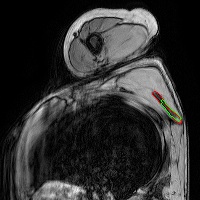

Refer to captionRefer to captionRefer to captionRefer to captionRefer to captionRefer to captionRefer to captionRefer to captionRefer to captionRefer to captionRefer to captionRefer to captionRefer to captionRefer to captionRefer to captionRefer to captionRefer to captionRefer to captionRefer to captionRefer to captionRefer to captionRefer to captionRefer to captionRefer to captionRefer to captionRefer to captionRefer to captionRefer to captionRefer to captionRefer to captionRefer to captionRefer to captionRefer to captionRefer to captionRefer to captionRefer to captionRefer to captionRefer to captionRefer to captionRefer to captionRefer to captionRefer to captionRefer to captionRefer to captionRefer to captionRefer to captionRefer to captionRefer to captionRefer to captionRefer to captionRefer to captionRefer to captionRefer to captionRefer to captionRefer to captionRefer to captionRefer to captionRefer to captionRefer to captionRefer to captionRefer to captionRefer to captionRefer to captionRefer to captionRefer to captionRefer to captionRefer to captionRefer to captionRefer to captionRefer to captionRefer to captionRefer to captionUNetCAE-UNetcGAN-UNetProposed method

Fig. 3: Automatic pathological segmentation of scapula using UNet [1], CAE-UNet [5], cGAN-UNet [8] and proposed method. Groundtruth and estimated delineations are in red and green respectively. In the first comparison, UNet under-segments the bone area, whereas other approaches achieve more accurate scapula delineations. In the second example, the proposed method captures more complex bone shape and subtle contours compared to other architectures.